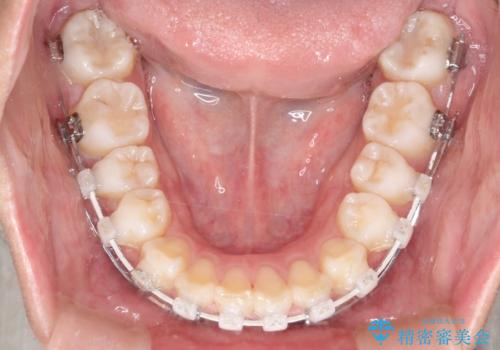

- 矯正装置

- 審美装置

- 出っ歯を主訴に来院されました。

下の歯並びに対して、上の歯が全体的に前方に位置している状態でした。

上の歯の前から4番目の歯を2本抜歯して、そのスペースに前歯を移動させて、前歯を引っ込める計画としました。